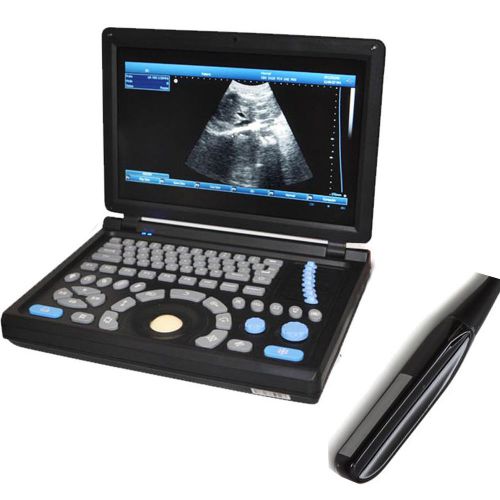

10.4'' Veterinary Digital Laptop PC Ultrasound Scanner with Rectal Probe 3D

Veterinary Digital Ultrasound Scanner CMS600P2+2 Probes(3.5Mconvex+6.5M rectal)

Full Digital Laptop Vet Ultrasound Scanner + convex probe+external 3D Animal use

Full Digital Laptop Vet Ultrasound Scanner +Micro convex probe + external 3D FDA

Veterinary Portable Ultrasound with Transducer - USA - Free carrying bag